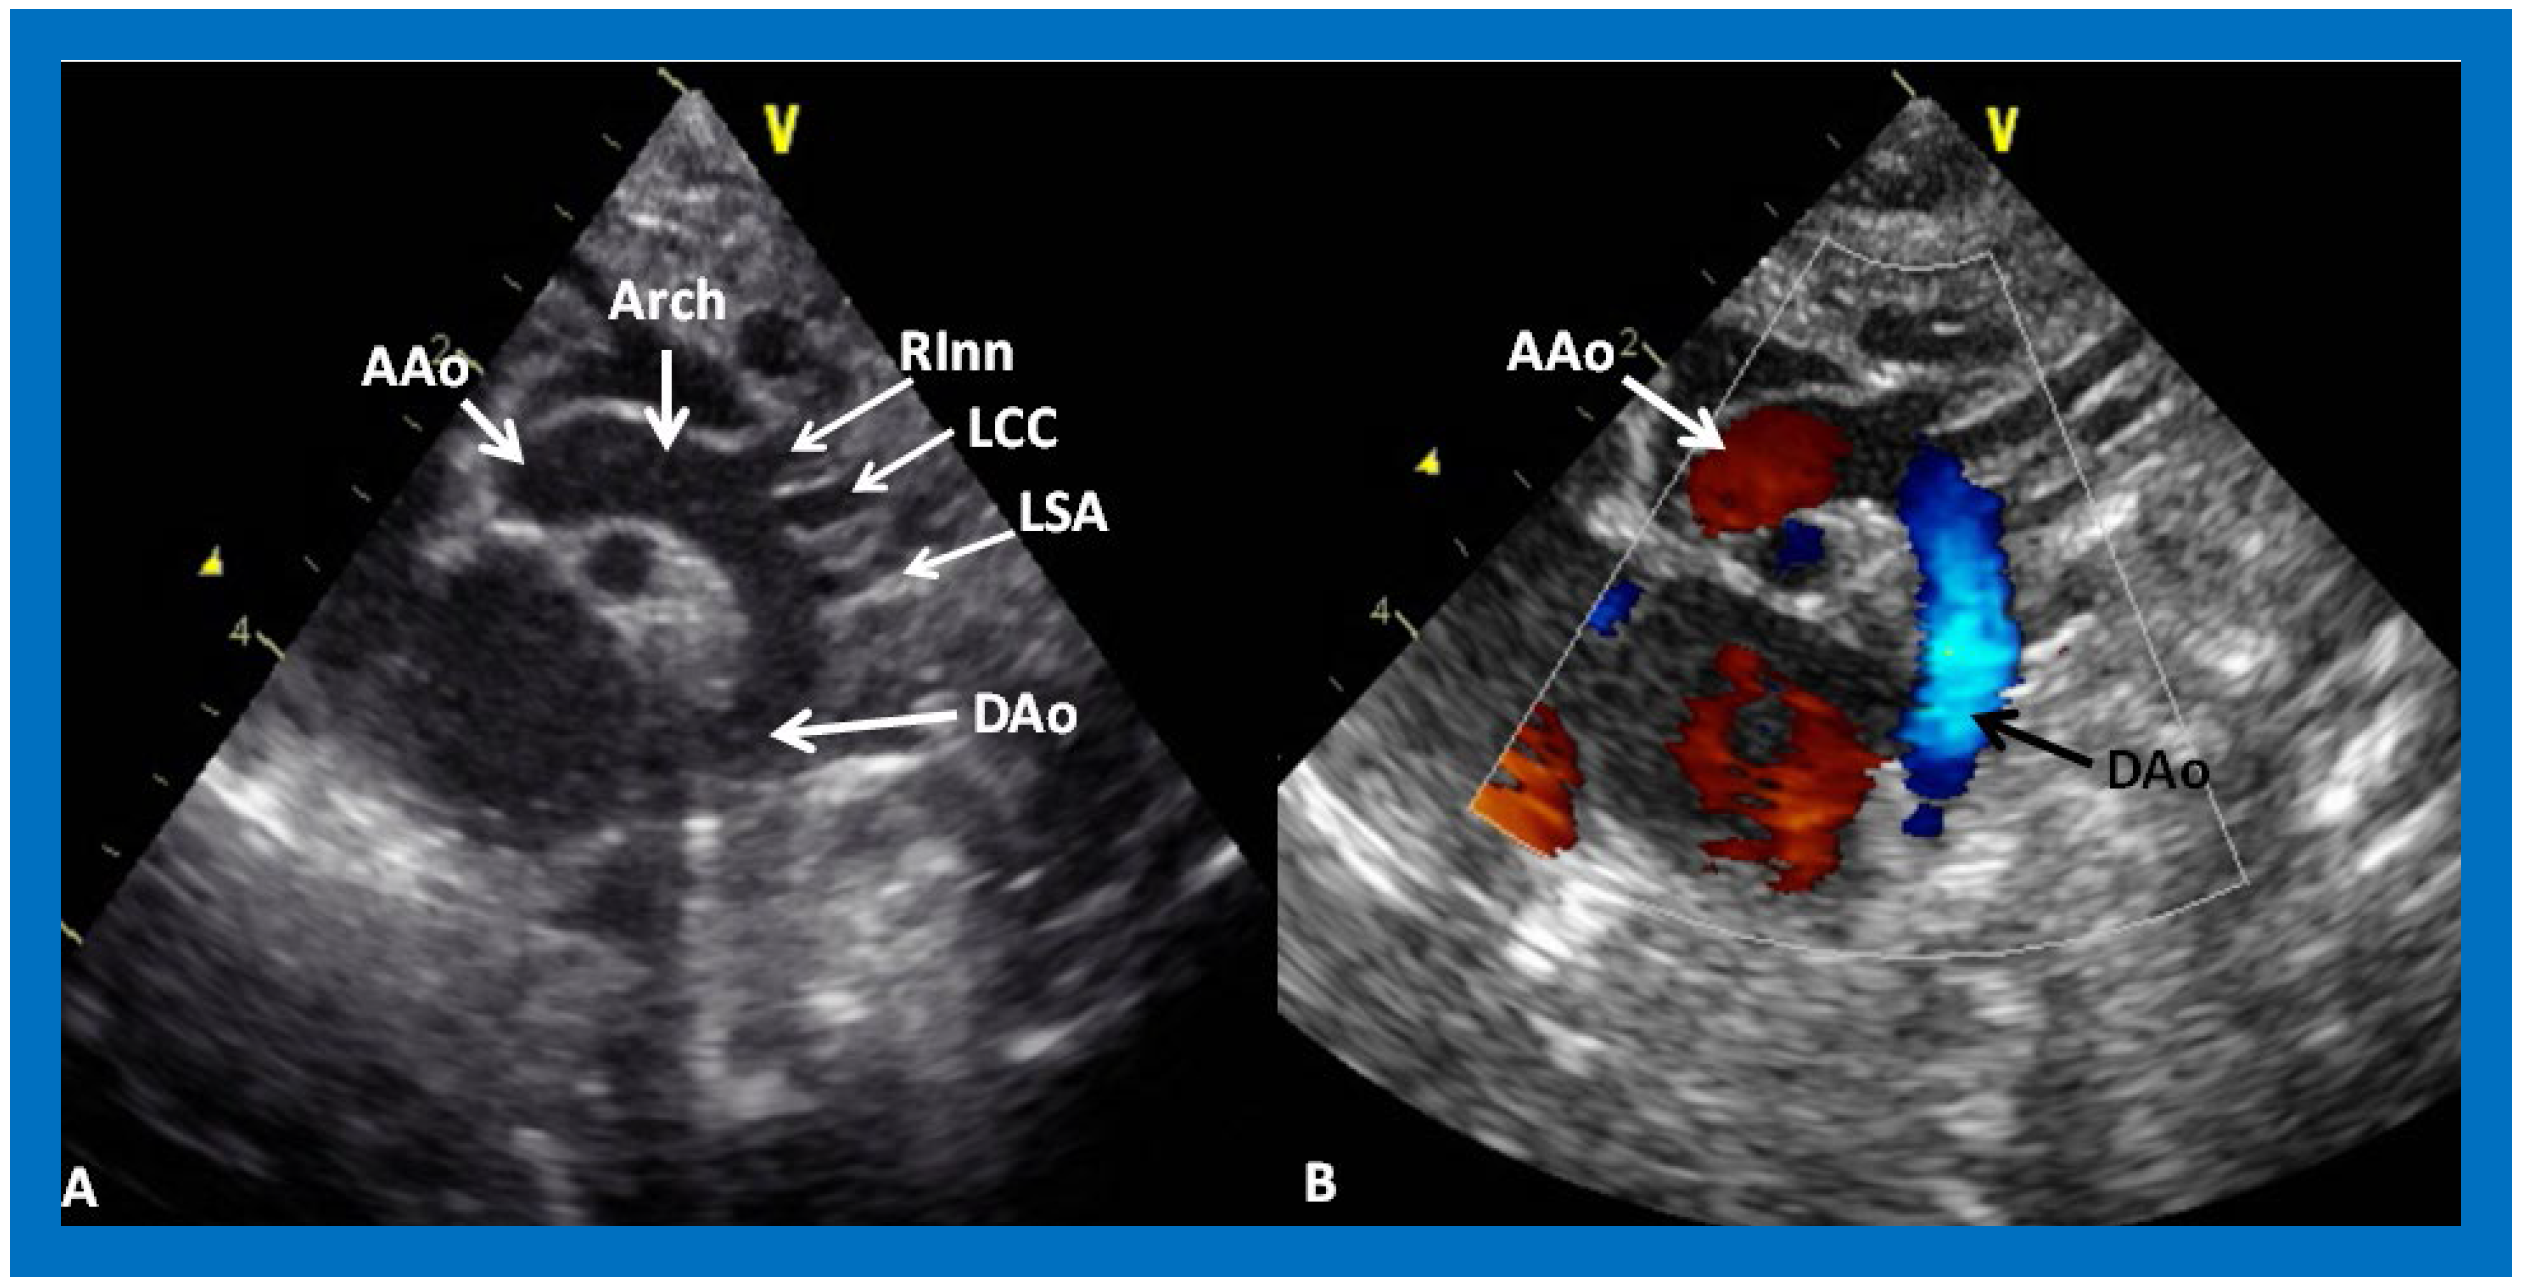

Figure 31. (A) Suprasternal notch view of a normal aortic arch (Arch) demonstrating the ascending aorta (AAo), aortic arch (Arch) and descending aorta (DAo). Note the origin of the right innominate (RInn), left common carotid (LCC) and left subclavian (LSA) arteries, arising from the aortic arch. (B) The same view with color Doppler imaging, showing red flow in the AAo and blue flow in the DAo. Reproduced from Reference [53].

Coarctation of the aorta is particularly common in Type II (transposition of the great arteries) patients; if present, it is usually dealt with at the time of initial palliation in the neonatal period. It is possible that coarctation was missed at the time of initial presentation or it may have developed subsequently. Alternatively, recoarctation may have developed following prior surgery or balloon angioplasty. Echo studies should be scrutinized to demonstrate the patency of the descending aorta (Figure 31) and, if coarctation is demonstrated (Figure 32; Figure 33), it should be treated either by balloon angioplasty or surgery, as deemed appropriate [38].